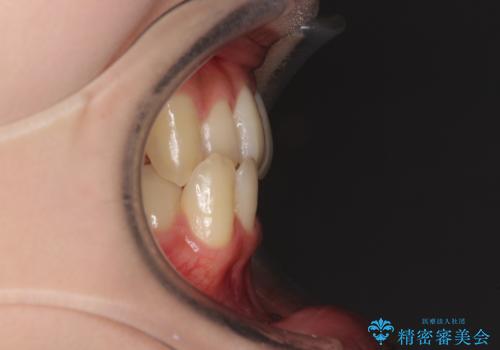

- 奥歯の反対咬合を気にして来院された患者様です。

反対咬合は上顎骨の幅が下顎骨よりも小さいことが原因なので、拡大装置により骨幅を広げて上下関係を改善し、その後インビザラインにて歯並びを整えることとしました。